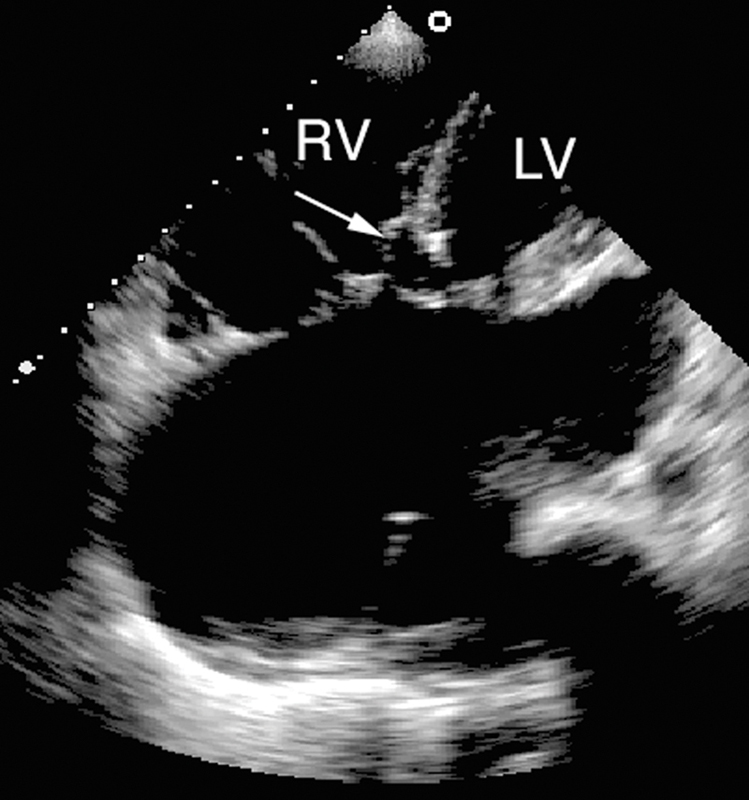

فحوصات تشخيصية لبعض امراض القلب والشرايين التاجية